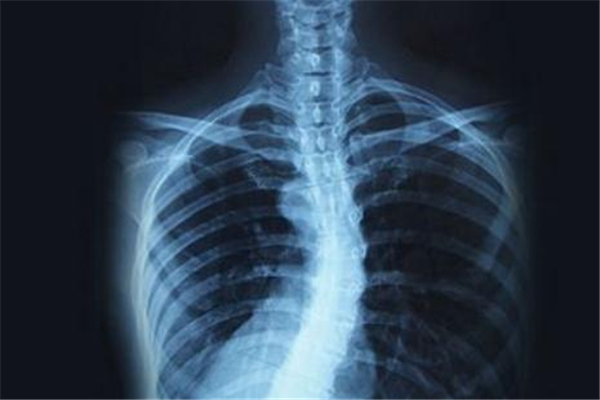

僵直性脊椎炎是一種病因不明,慢性的全身性發(fā)炎疾病,最主要是侵犯脊椎關(guān)節(jié)以及附近肌腱、韌帶等軟組織,影響到中軸骨及接骨點(diǎn)的肌腱或韌帶的慢性病,這種病會(huì)使身體脊椎鈣化僵硬,因?yàn)闀?huì)造成畸形、駝背,脊椎黏合后因喪失柔軟度,變得較易骨折或因而造成神經(jīng)壓迫,就像是脆弱的竹竿一樣無法順利彎曲,所以又被稱為竹竿病,同時(shí)也有家族遺傳的傾向。

它是一種不可逆的疾病,一旦發(fā)生就會(huì)持續(xù)惡化下去,從一開始的下背痛,脊椎、髖骨、骨盆薦骨發(fā)炎,接下來出現(xiàn)骨點(diǎn)及關(guān)節(jié)鈣化、僵直的情形,然后再發(fā)生脊柱無法彎曲、失去彈性,到最終發(fā)炎及僵直的情況會(huì)向脊椎上下蔓延,這種發(fā)展實(shí)在是很嚴(yán)重,輕忽不得。